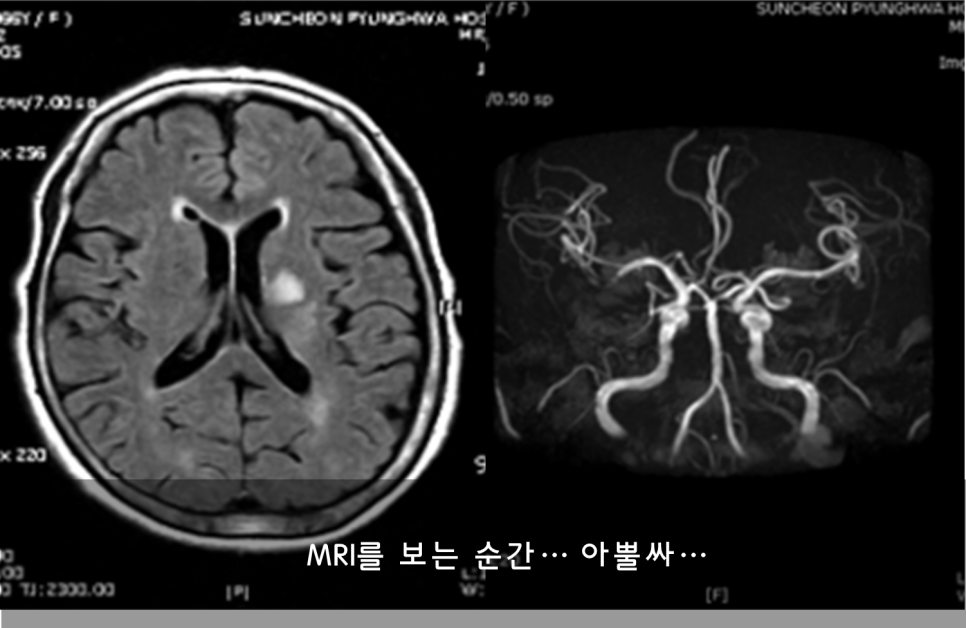

아뿔싸, 큰 일이다. 뇌졸중이다!!!

바로 동산의료원 신경과 후배에게 전화를 하고 장모님을 모시고 응급실로 달려갔다. 그래도 그때까지 장모님은 팔다리에 힘은 괜찮으셨다. 그러나 응급실에서 MRI 검사를 하고 뇌경색으로 판정이 나고 하는 과정에서 조금씩 오른팔에 기운이 떨어지기 시작했다.

지금 생각해 보면 첫날 전화받을 당시는 일과성 허혈이라고 해서 뇌혈관이 잠깐 막혀서 증상이 생겼던 것 같다. 그러다가 다시 혈관이 재개통되면서 증상이 좋아졌다가 다음날 아침 재경색이 온 것으로 생각된다. 흔한 경우는 아니지만 아주 드문 일도 아니다. 일과성 허혈이 있은 뒤 바로 몇 시간 뒤 진짜 뇌경색이 온 셈이다.